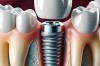

韩国在种植牙领域发展迅速,其品牌以其较高的性价比、良好的临床效果和广泛的市场覆盖而闻名,在全球范围内(包括中国)都非常受欢迎,以下是一些主要的韩国种植牙品牌:🦷1.登腾(Dentium)市场地位:目前全球市场占有率最高的韩国种植牙品...